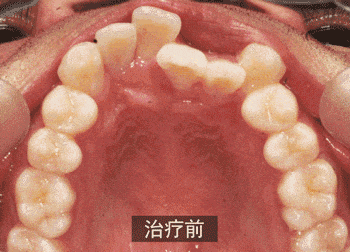

关于牙齿矫正的15个秘密!不看就只能被蒙在牙缝了!

很多人都想拥有一口完美的牙齿,但对于牙齿矫正,大家似乎总有一些不全面的认识。

牙齿矫正其实是个相当复杂的过程,正确认识牙齿矫正,并找到适合自己的方案,才是最理想的选择!

矫正牙齿一定要拔牙吗?

有些人矫正牙齿确实是需要拔牙滴,毕竟拔牙可以把一部分空间空出来,让拥挤的牙齿有个地方呆。

但“给出空间”并不仅仅是通过拔牙来解决,前后向或左右向扩展牙弓、片切(适度把牙磨窄),这些都能达到目的。

害怕拔牙的朋友别担心,矫正牙齿可不是一定要拔牙。但如果不拔牙无法达到理想效果时,也不要犹豫了。

拔牙校正后一定有牙缝?

牙齿为什么要矫正?因为不整齐!牙齿为什么不整齐?因为有些牙齿挤在一起,有些牙齿离得却太远。

矫正牙齿的目的就是为了“合理利用空间”。只要是对的正畸方法,最终都能让每颗牙齿拥有恰到好处的“占地面积”。

所以说,最终排列好的牙齿绝不会留有传说中的“很大的牙缝”。